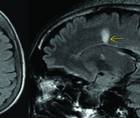

Radiologic Biomarkers in Multiple Sclerosis: Improving Detection and Diagnosis

Practical Neurology: Focus on Multiple SclerosisRadiologic Biomarkers in Multiple Sclerosis: Improving Detection and Diagnosis